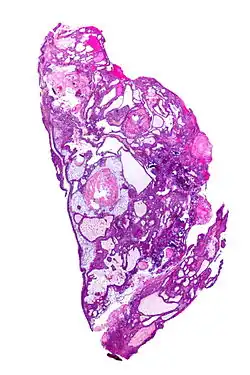

| Very low magnification micrograph of an adamantinomatous craniopharyngioma. HPS stain. | |

Micrograph showing the characteristic features of an adamantinomatous craniopharyngioma - cystic spaces, calcifications, and "wet" keratin, HPS stain -